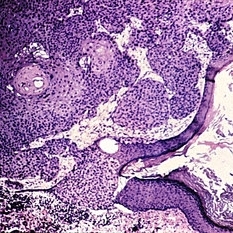

Slide 5-19

Keratinizing epithelium lining a dermoid cyst in the center, with keratin contents and a single large hair above. The connective tissue wall has a large hair follicle in it.

Condition/keywords: cyst, epithelium